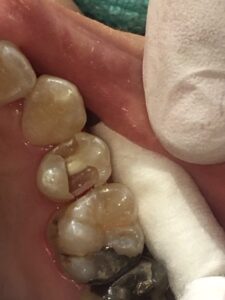

MTAセメントにて覆髄しました。

ダイレクトボンディングにて修復しました。